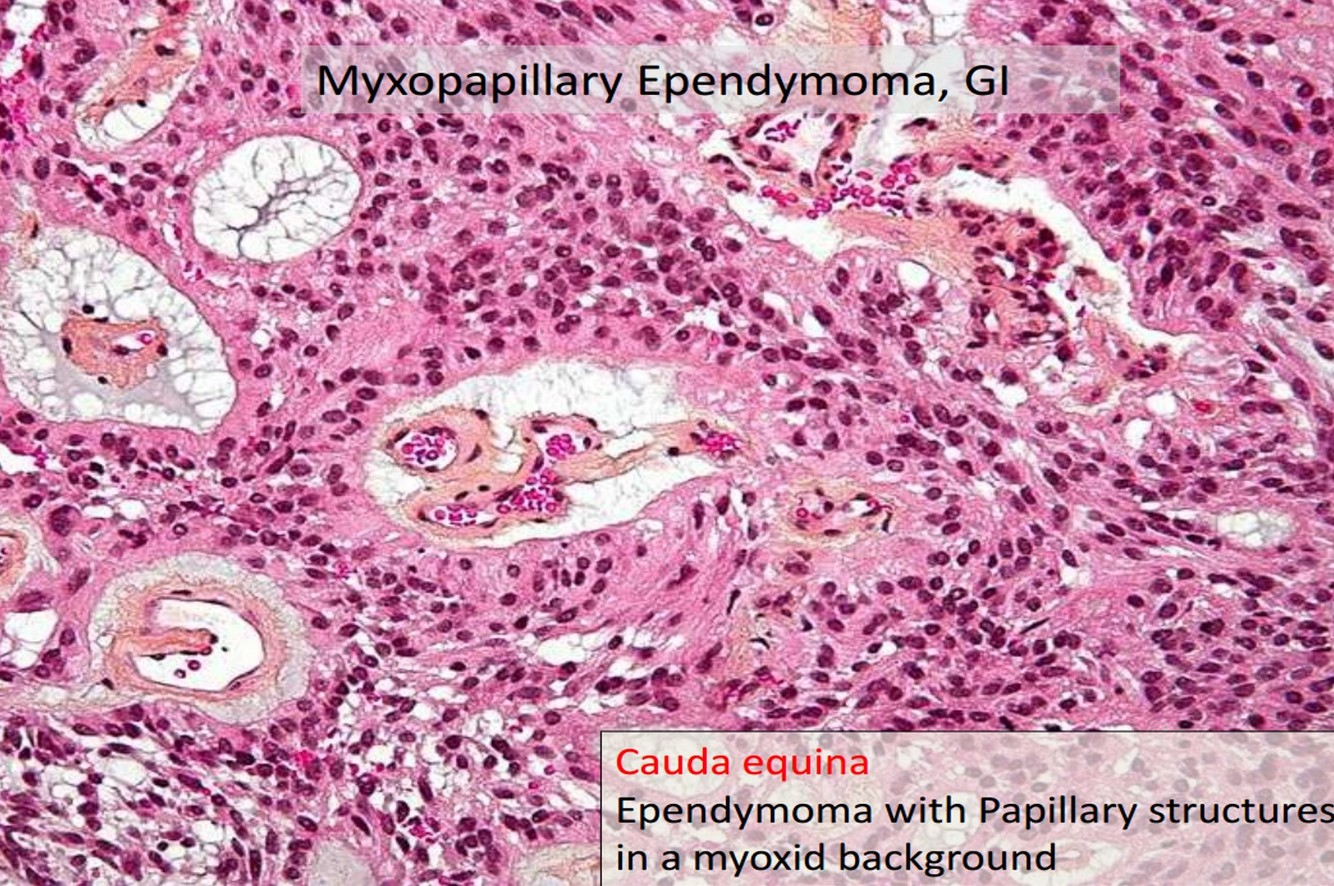

Ependymoma

- Incidence: 5% to 10% of primary brain tumors in the 1st two decades

- Arise around ventricular lining

- Locations:

- The 4th ventrical: common in children

- Spinal: adults, mean 40 yrs, NF2

- Loss/mutation of NF2 on chromosome 22q in spinal cord tumors